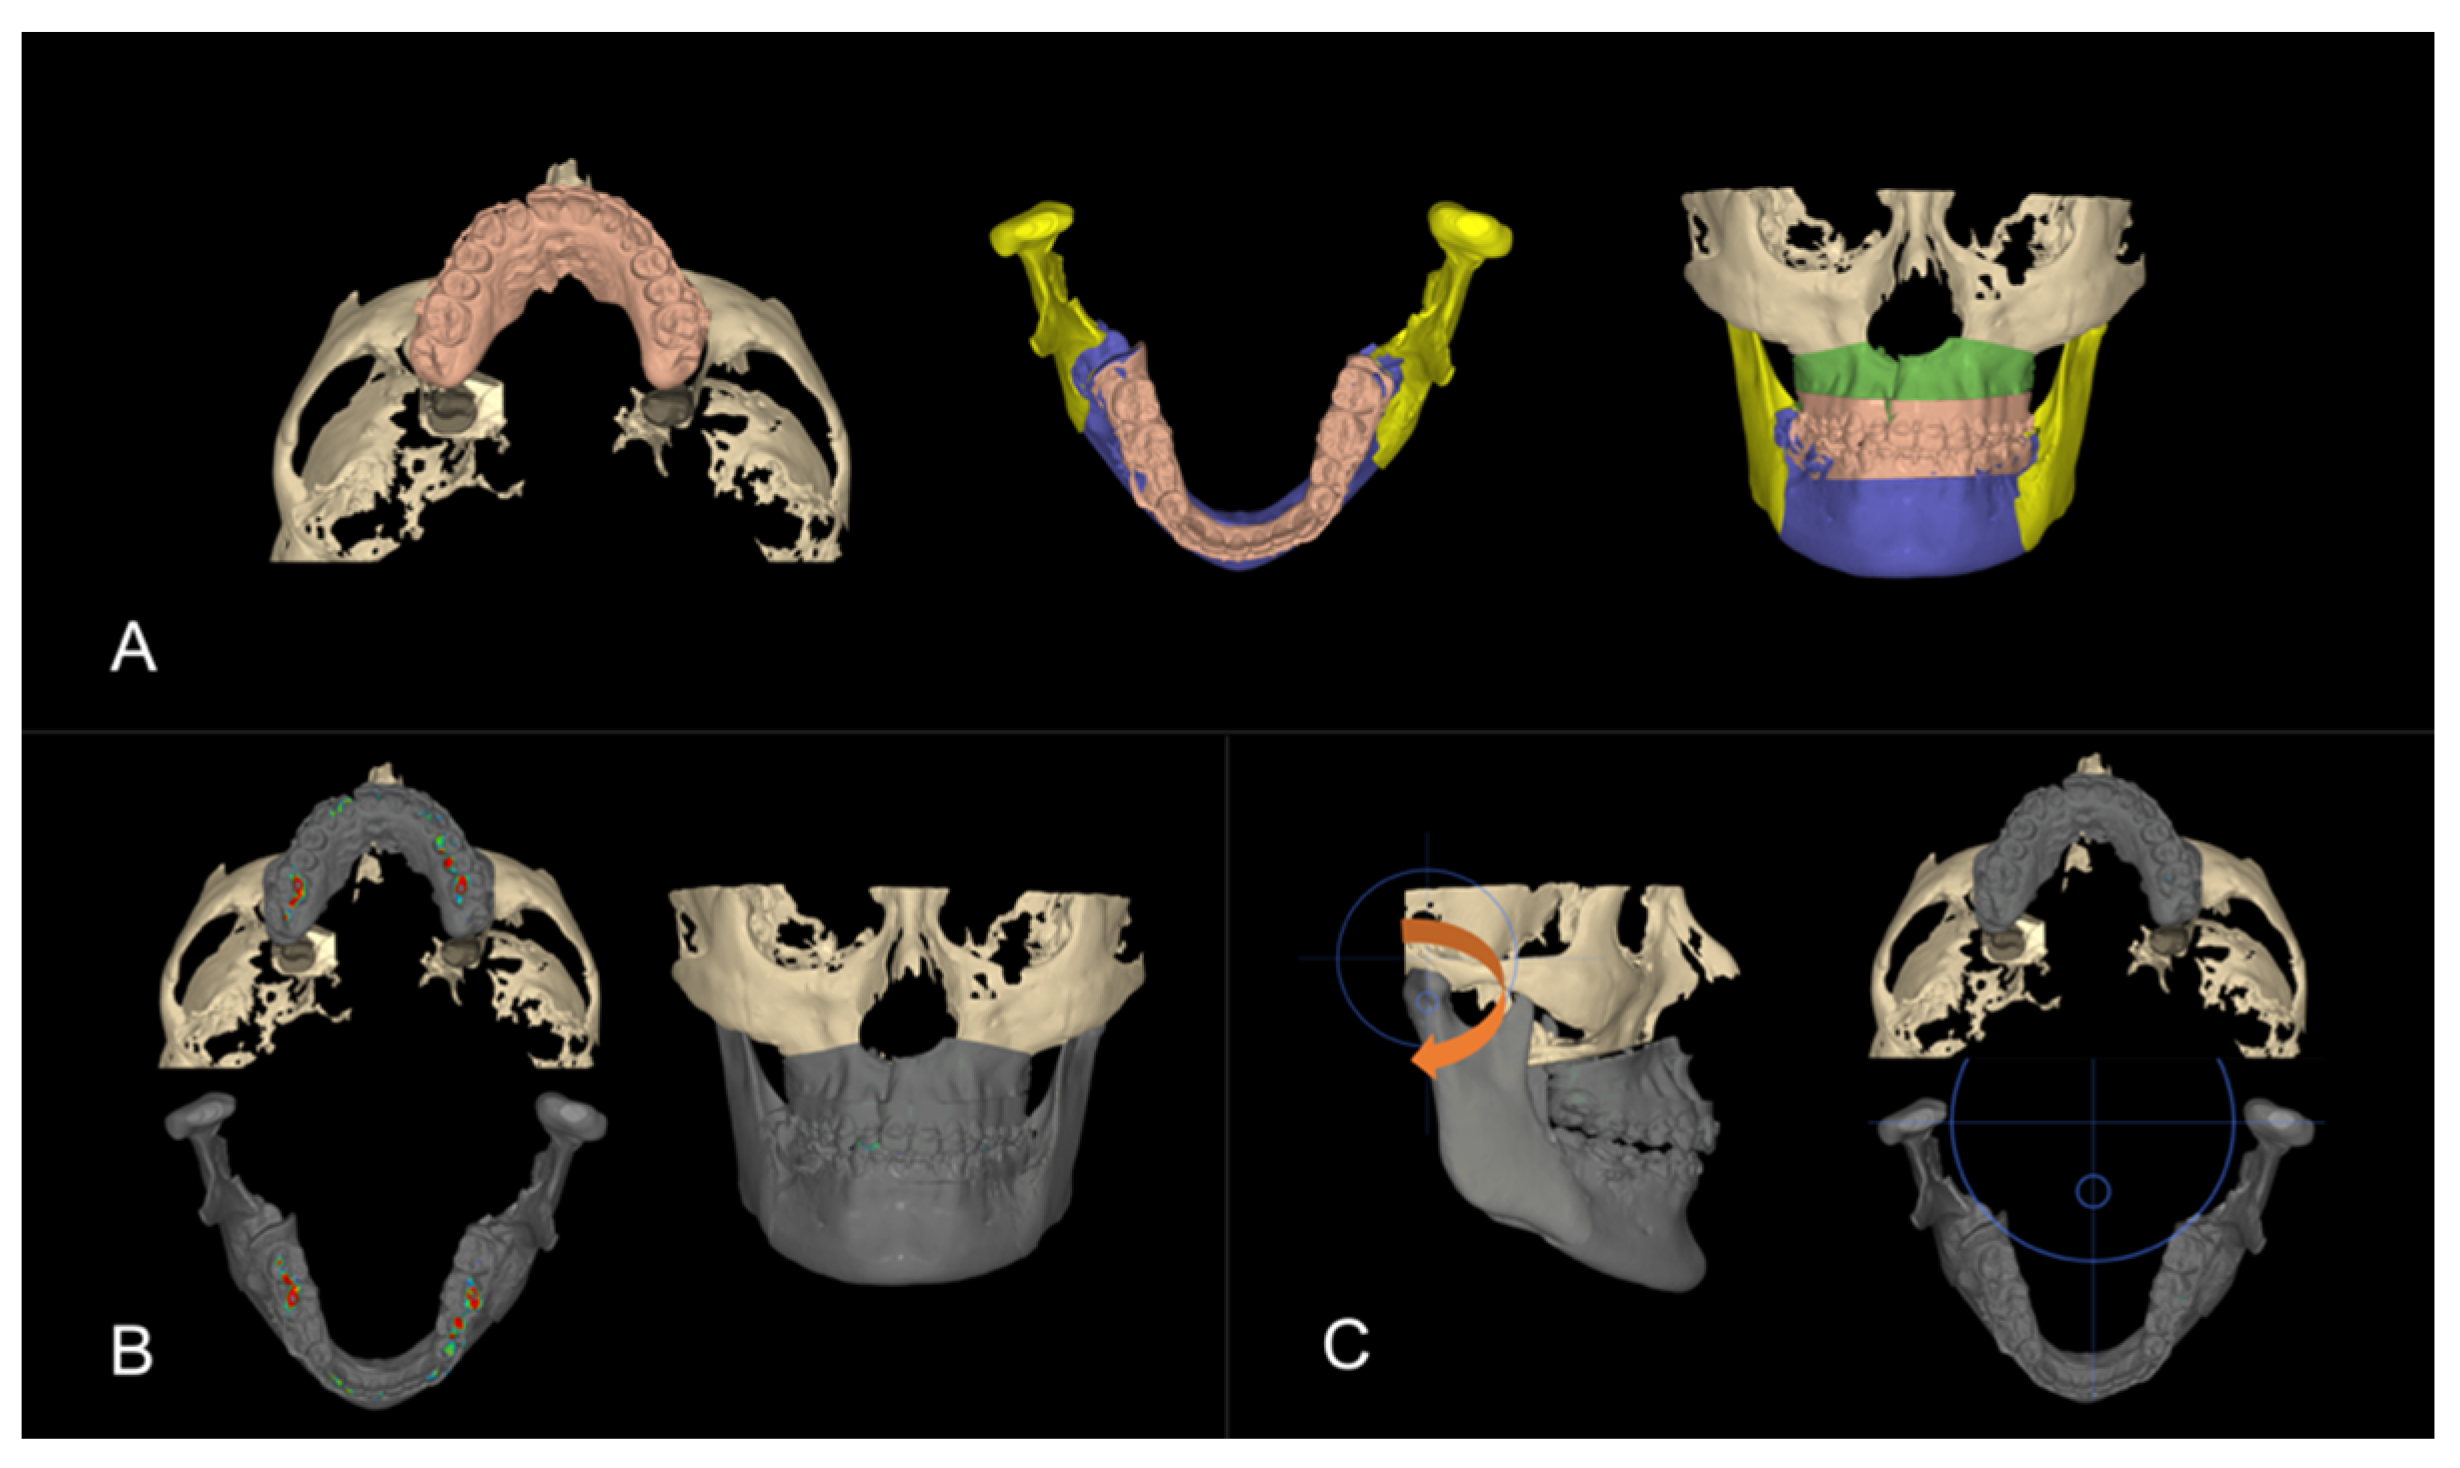

3. Virtual Treatment Planning

3.1. Step 1: Virtual Orthodontic Setup

3.2. Step 2: Virtual Surgical Repositioning

3.3. Step 3: Reverse Engineering the Transitional Occlusion